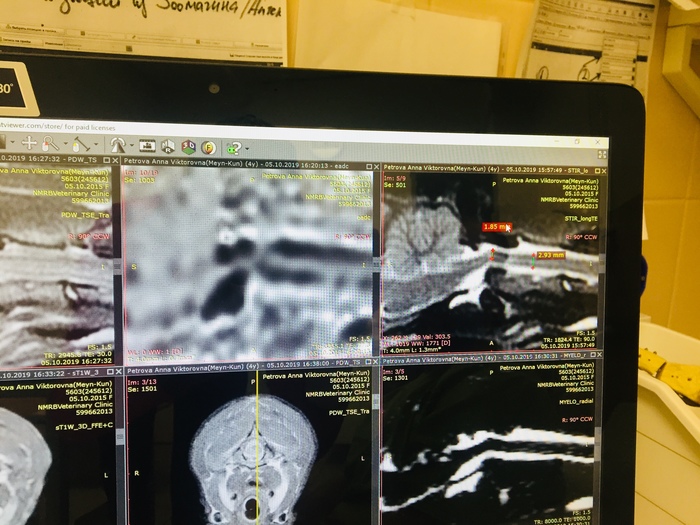

Всем привет! У меня есть кот, подобрал пару лет назад, сбитого, на обочине, без сознания. Сначала он был совсем не очень живым, но после двух недель в стационаре вроде поправился(немного шокирован был от того сколько стоит лечение). После того, как забрал домой, кот понятное дело долго приходил в себя, ходил не очень уверенно, не очень понимал что происходит. Периодически были видны последствия черепно-мозговой травмы(невозможность сконцентрироваться на одном объекте, я так понял, т.к он постоянно провожал взглядом непонятно что с одной стороны в другую и так по кругу(хз как по другому объяснить). Потом окреп и стал более уверенным, есть еще кошка и кот, с котом подружился, с кошкой до сих пор нет. Так вот проблема в том, что после того как он более менее пришел в себя - начал ходить по квартире и просто кричать, сначала было терпимо, потом невыносимо. Купил успокоительные в вет. аптеке - вроде сначала успокаивали, потом какие то нервные срывы бесконтрольные начались, перестали давать таблетки. Прошло какое то время и он стал обычным ленивым котом. Но пару месяцев назад он опять начал ходить из угла в угол и орать, мы уже привыкли, но хочется это изменить, он может несколько часов подряд ходить и кричать, потом дышит как пес, отдохнет 10-20 мин и опять ходит. Если знаете, что делать или к какому конкретно врачу обратиться - подскажите пожалуйста. Учитывая невозможность проверить чисты ли на руку вет. клиники, хотелось бы сразу попасть к нужному специалисту, а не выкинуть много денег на обычные - «У вас отличный кот, спасибо, что показали». Спасибо. Плюсаните пожалуйста, хочется, чтобы Олег перестал переживать)